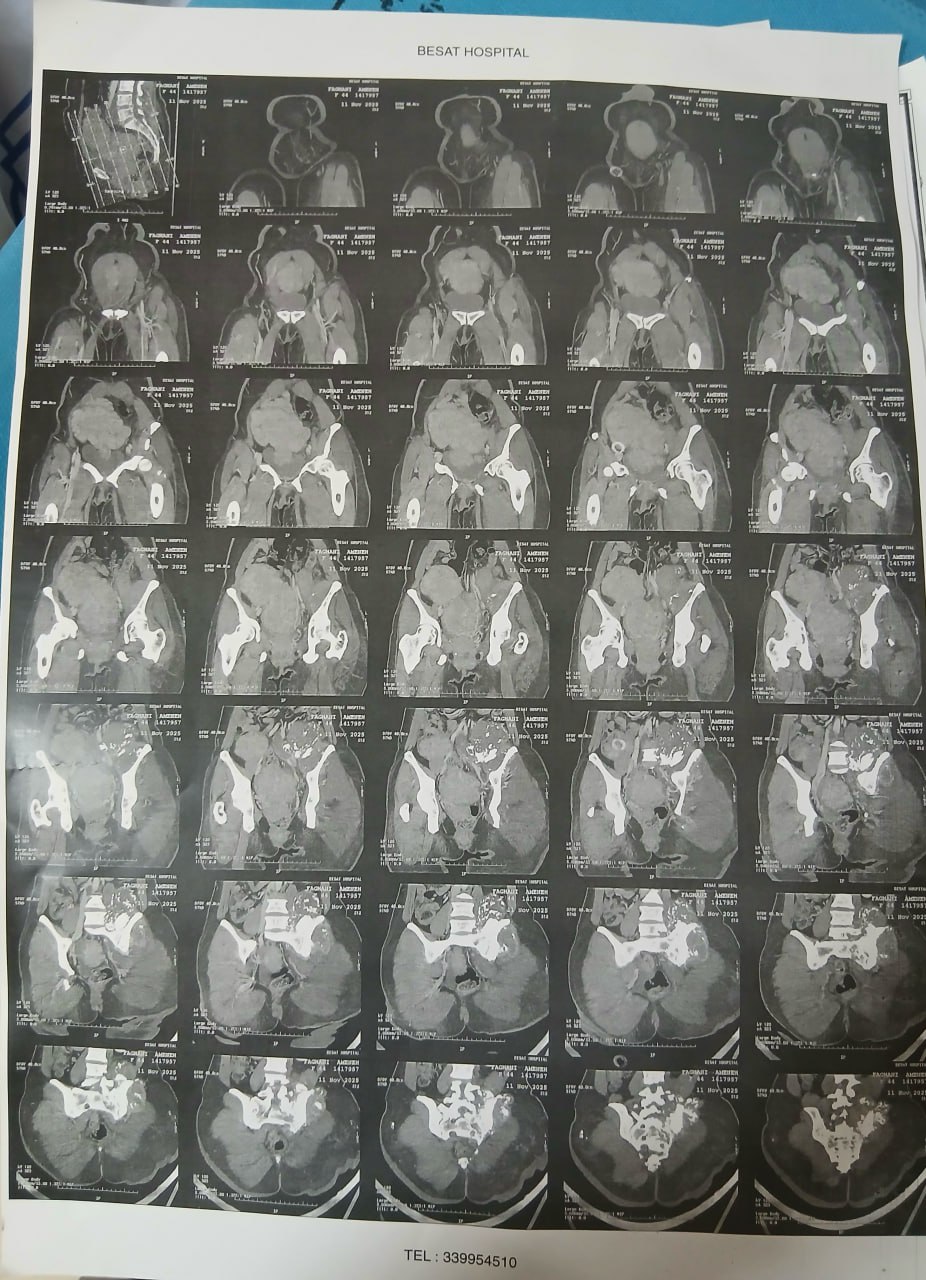

در بررسیهای تصویربرداری (MRI)،در تاریخ 24.7 ، تودهای با تشخیص کندروسارکوما همراه با DVT گزارش شده است. بیمار سابقه درد لگن داشته که شدت آن در حال حاضر نسبت به گذشته کاهش یافته است. به گفته بیمار، حجم توده در ابتدا در حدود اندازه یک تخممرغ بوده که در حال حاضر کاهش یافته است. همچنین تورم اندام تحتانی در حال حاضر نسبت به قبل کمتر شده است.

مراجعه کرده است. پس از بررسی های انجام شده در MRI انجام شده توده با درگیری مفصل ساکروایلیاک چپ و DVT؛ ابتدا تحت درمان DVT قرار گرفته است و سپس جهت پیگیری تومور رویت شده تحت بیوپسی قرار گرفته است و با تشخیص کندروسارکوما به این مرکز مراجعه کرده است و تحت کموتراپی و رادیوتراپی قرار گرفته و سایز تومور کاهش یافته است.

(تصویر مربوط به این مراجعه نیست) Other: